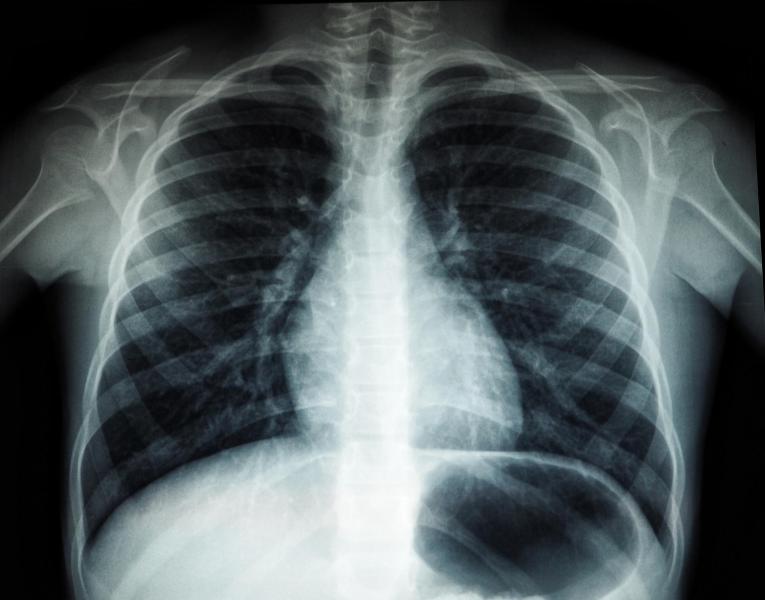

После этого мужчина решил все же пройти обследование и отнес снимок легких в медицинское учреждение.

Ранее также через суд обязали сделать флюорографию жителя Самары. Он знал, что должен проходить обследование не реже двух раз в год, поскольку состоял на туберкулезном учете.